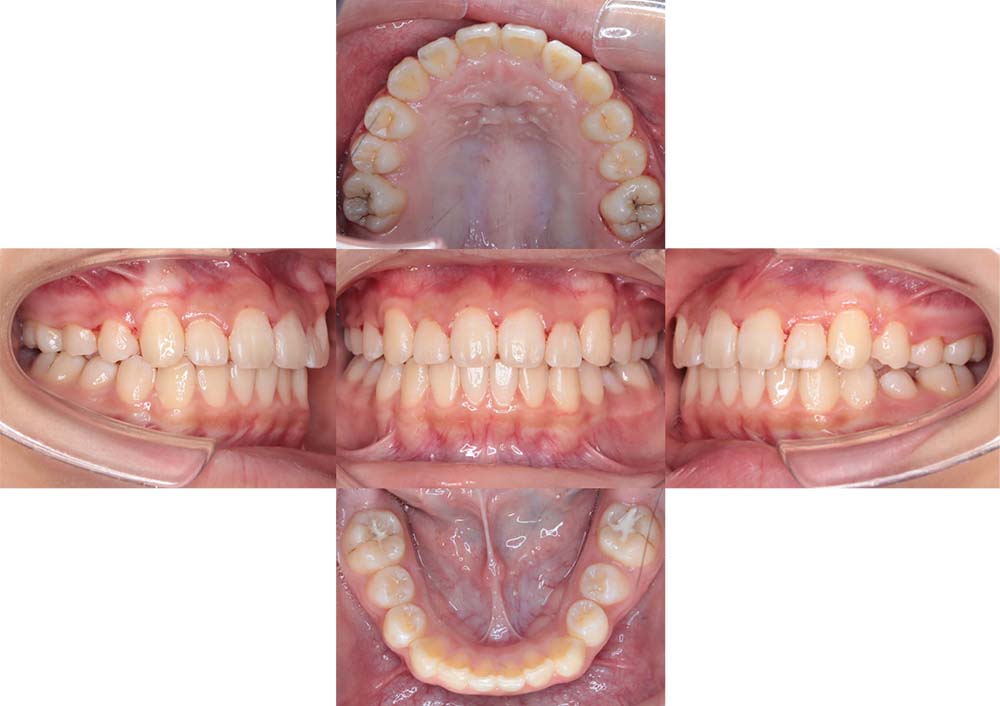

症例03

| 主訴 | 歯並びがガタガタしている。 |

| 診断名あるいは主な症状 | 過蓋咬合、叢生 |

| 年齢/性別 | 26歳・女性 |

| 矯正ステージ | 大人の矯正治療 |

| 治療方法 |

ワイヤー矯正 歯科矯正用アンカースクリュー(3本) |

| 抜歯部位/抜歯有無 | 抜歯 |

| 治療内容 | 上下顎の奥歯を後方に移動後、ガタガタの改善と上下顎前歯を後退させた。 |

| 費用 |

90万円程度(2025.10時点の料金となります。) ※矯正基本料金、アンカースクリュー、審美ブラケットを含む |

| 治療期間 | 2年8ヶ月 |

| 主なリスク・副作用 | 痛み、歯根吸収、歯肉退縮、虫歯、後戻り |